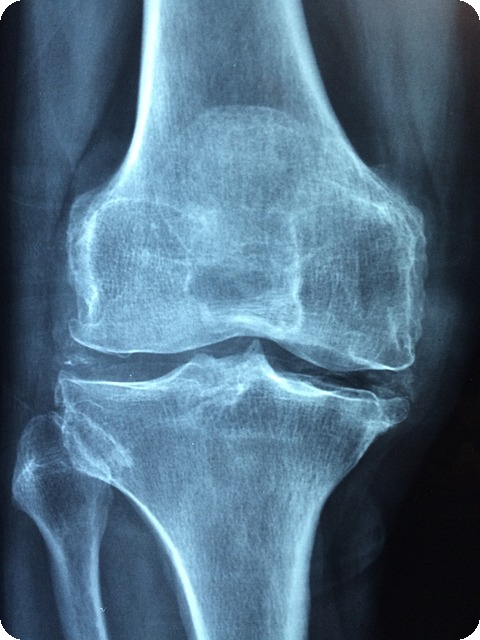

퇴행성 관절염

퇴행성 관절염, 또는 골관절염은 무릎 통증의 가장 흔한 원인으로, 주로 중년 이후에 발생합니다. 무릎 연골이 점차적으로 소실되면서 뼈끼리 마찰이 일어나고 염증이 발생하게 됩니다. 이로 인해 통증, 뻣뻣함, 부기 등의 증상이 나타납니다.

"퇴행성 변화는 피할 수 없는 노화의 일부이지만, 적절한 관리로 증상을 완화할 수 있습니다."

퇴행성 관절염의 증상은 특정 활동, 예를 들어 계단을 오르내리거나 쪼그려 앉을 때 더욱 심해지는 경향이 있습니다. 따라서 운동량 조절과 규칙적인 운동이 중요합니다.